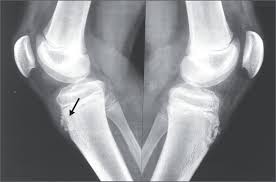

A másik gyakori panaszt okozó eltérés az un. Schlatter-osgood syndroma, melynek lényege, hogy a combfeszítő izom térdkalács szalaggal közvetített tapadása a sípcsonthoz még nem csontosodott hozzá. Jellemzője a térd alatt a sípcsont elülső felszínén kialakuló fájdalmas duzzanat.

A diagnózis itt is fizikális vizsgálat és rtg felvétel készítése. Mindkét betegségebn nagyon ritkán szükséges kiegészírésként MR vizsgálat.